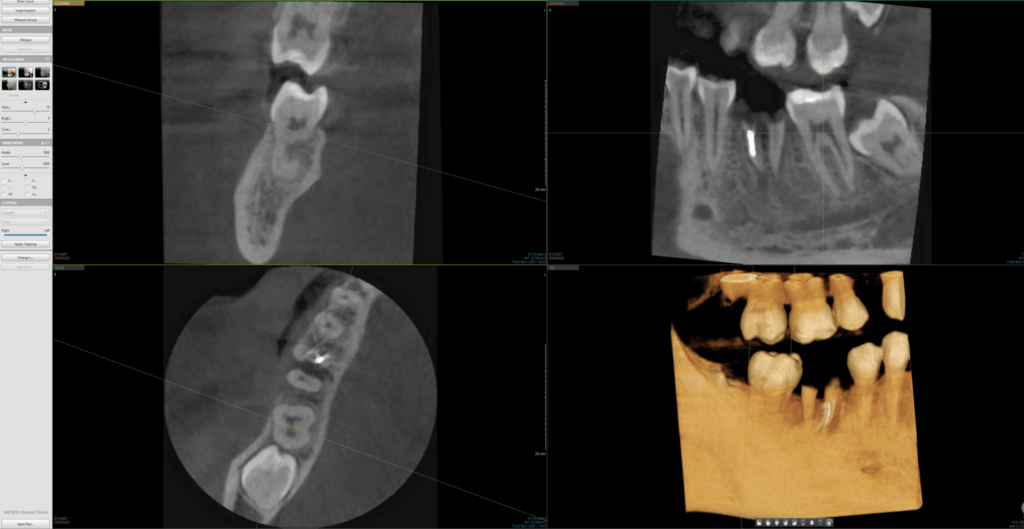

3D/CBCT (kompjuterizovana tomografija sa konusnim snopom) je napredni postupak snimanja u stomatološkoj radiologiji. Koristeći tehnologiju sličnu onoj kod standardnih medicinskih skenera, ali sa drastično smanjenom količinom zračenja, ova metoda pruža izuzetno precizne slike dentalnih struktura. 3D/CBCT omogućava pravljenje detaljnih trodimenzionalnih snimaka koji daju stomatologu potpuni uvid u zubne i koštane strukture, bez skrivenih ili iskrivljenih delova.

2D snimci su uobičajena vrsta snimanja koja prikazuje zube i vilice u jednoj ravni. To uključuje snimke pojedinačnih zuba, ortopane i slično. Za razliku od tradicionalnih 2D snimaka, 3D snimci zadržavaju pravilan odnos struktura, predstavljajući visinu, dužinu i širinu svih struktura u pravom odnosu 1:1.

Ova vrsta snimanja je posebno korisna za kompleksnije dentalne procedure, kao što su oralno-hirurške intervencije, postavljanje dentalnih implanata, ili tretman zuba sa višestrukim korenovima. Zahvaljujući 3D/CBCT snimcima, stomatolozi mogu precizno planirati i sprovoditi ove intervencije.